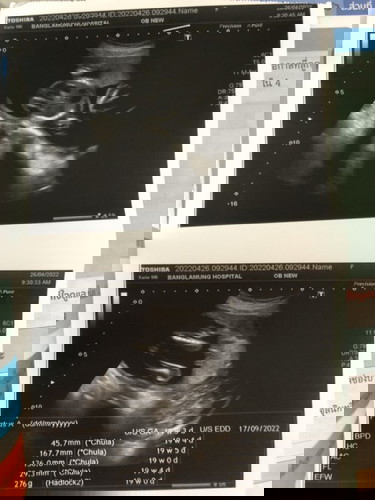

ตอนซาวด์หมอไม่ได้บอกเลย แต่ในภาพเหมือนมีก้อนขาวๆตรงเท้าน้อง ใช่จู้ๆมั้ยคะ

เหมือนจะเป็นไข่น้อนเลยค่ะแม่ 🤣